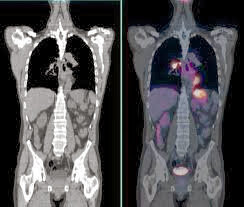

• Combinacion de PET con TC

Combinacion de PET con TC

Se comprobó que utilizando la imagen de un TAC de muy baja dosis asociado al equipo, se corregían con mayor precisión los problemas de atenuación intrínsecos a la imagen PET, y además dado que estas imágenes se podían obtener en cuestión de segundos, se disminuía el tiempo de exploración (se pasó de una media de 60-90 min a los 12-15 minutos actuales).